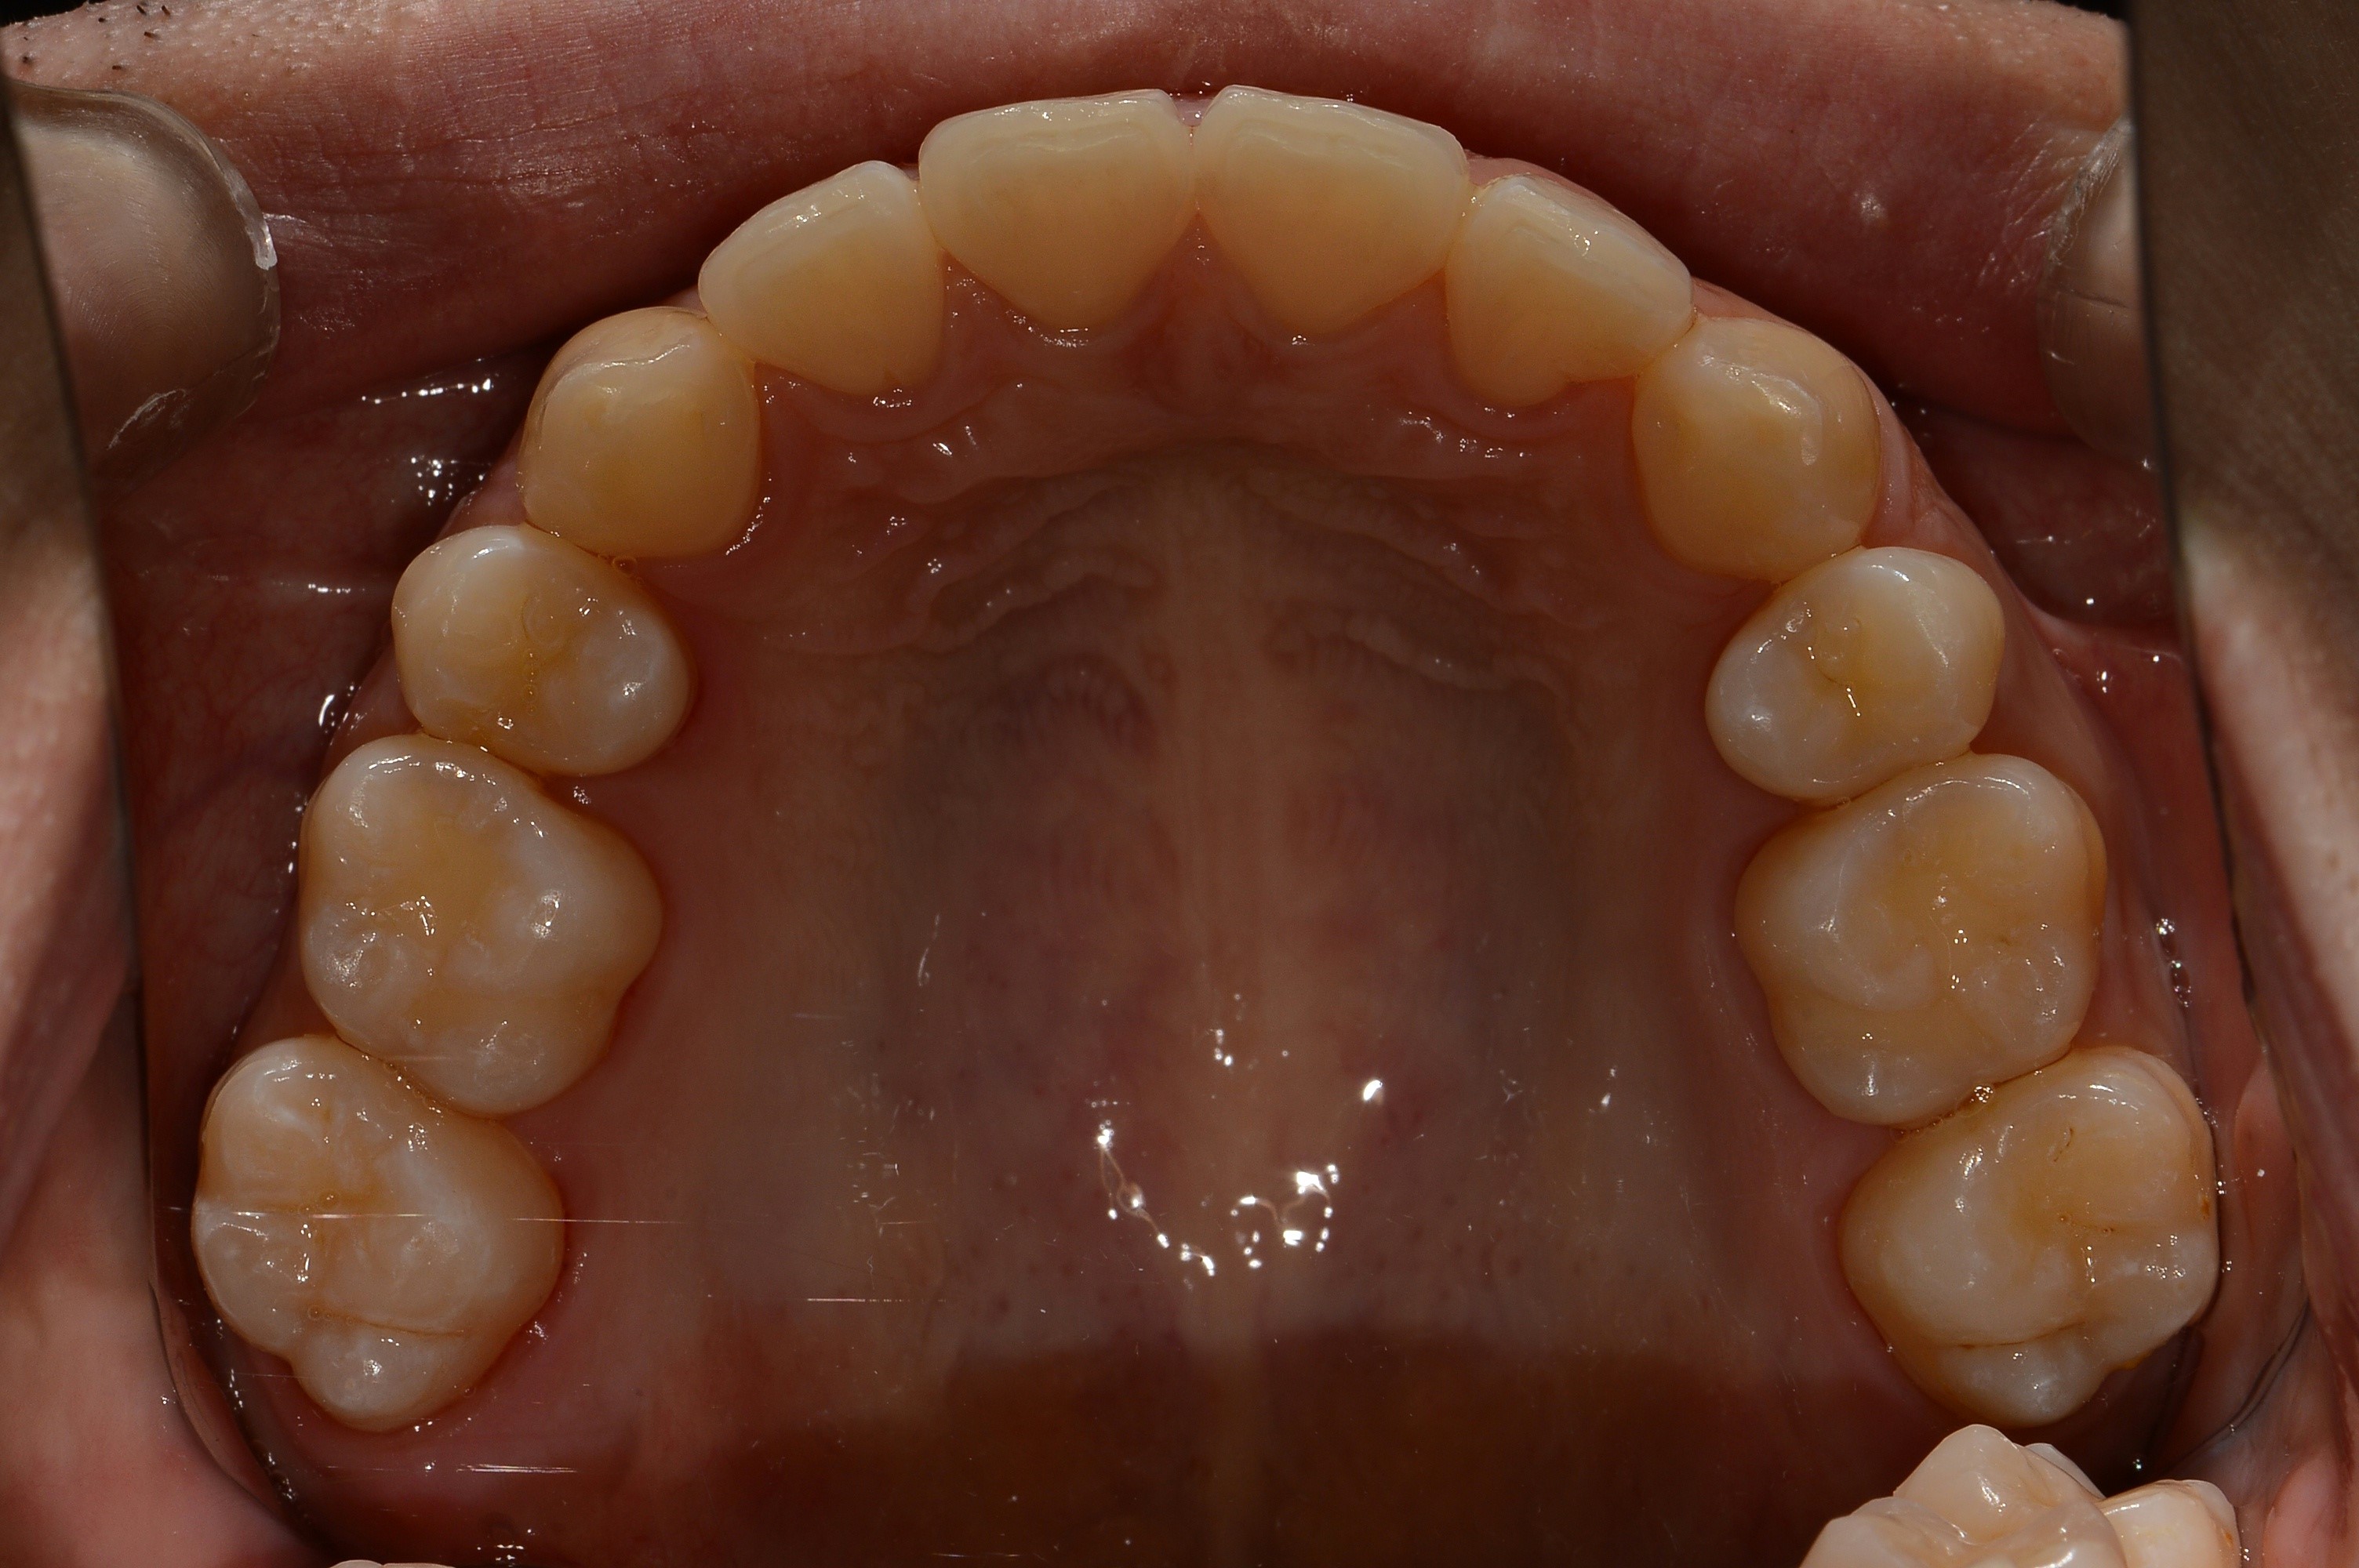

치료 후 사진입니다.